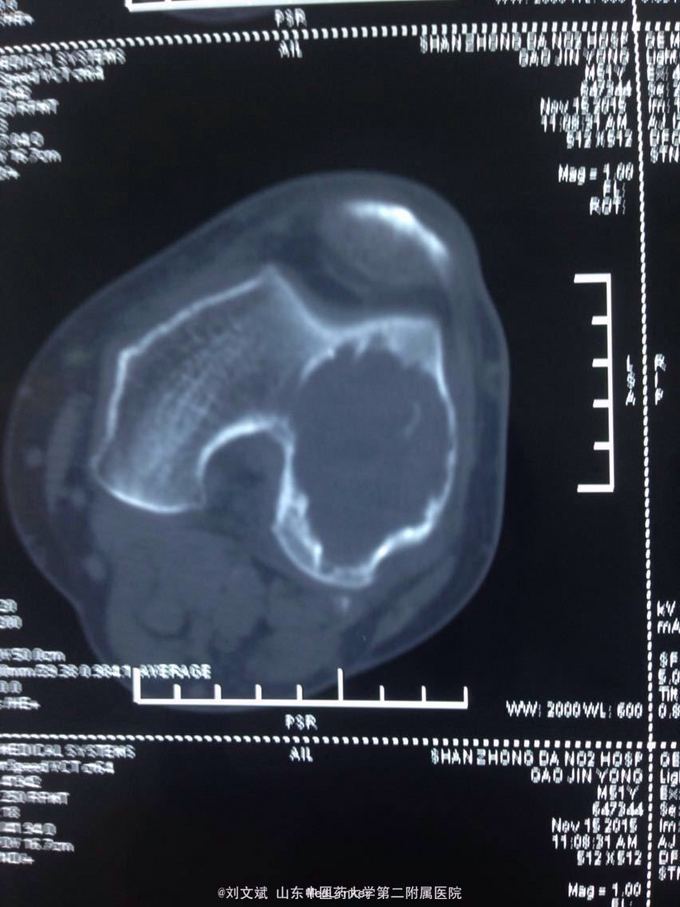

男性51岁,左膝关节疼痛不适10余年。因症状较轻,不影响活动,未曾系统诊治。一月前因扭伤致疼痛加重,拍片检查,见股骨远端骨质异常,进一步行CT示股骨髁占位病变,考虑骨囊肿。既往有高血压,糖尿病病史。近期无低热,体重下降。

左膝关节外观皮色正常,无明显肿胀,屈伸活动未见明显受限,外髁轻度压痛,侧方应力及抽屉试验阴性,半月板回旋挤压试验阴性,浮髌试验阴性。肢端感觉,血运正常。

诊断:左股骨远端占位 因皮质完整,行手术开窗刮除,自体髂骨及同种异体骨混合植骨填充治疗。切取组织送病理检查

刮除占位组织如图所示,送病理检查了,结果还没回来。 没有全身症状,像是原发灶,骨皮质完整,没有明显骨膜反应请专家们看看,什么可能性比较大? 补上病理结果和术后片子